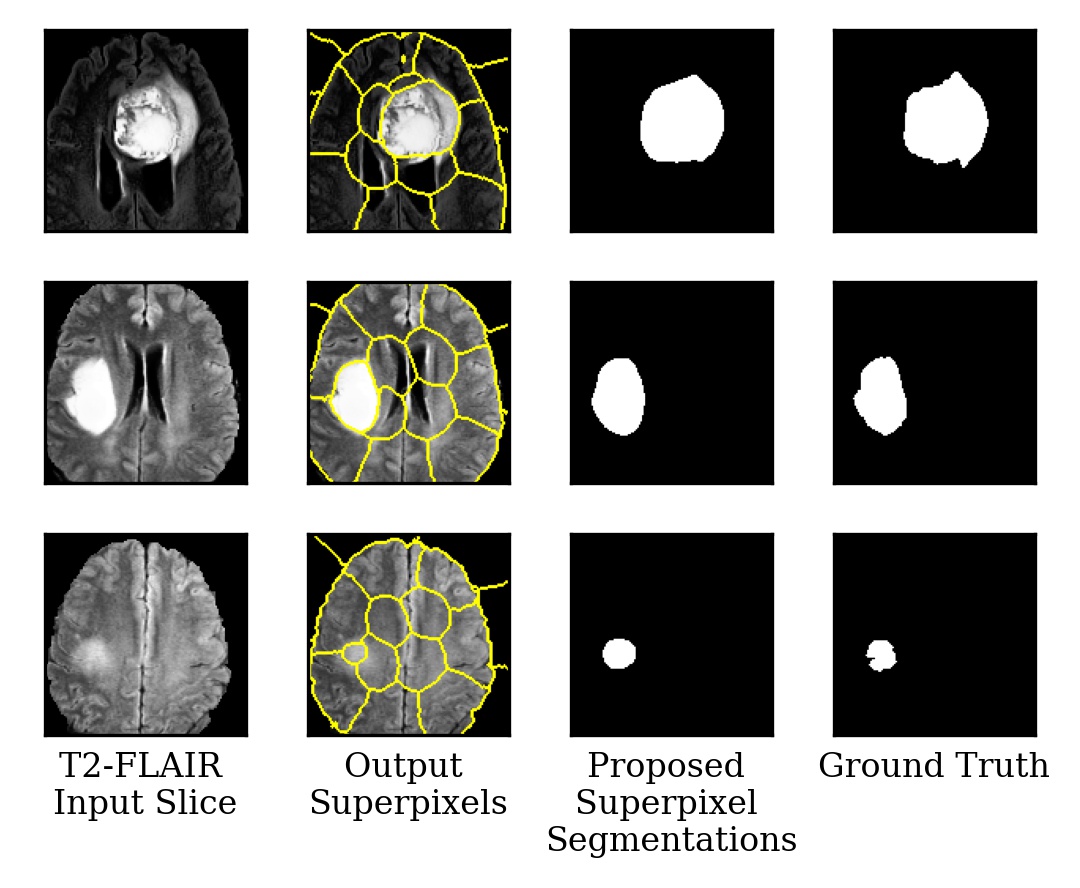

Figure 2 presents three images from the test set and their corresponding segmentations generated at each step of the pipeline, as well as the ground truth segmentations.

Figure 2: Visualization of T2-FLAIR channel of MR images, generated superpixels, output segmentations, and true segmentations for three examples.

Figure 2 demonstrates how the proposed method can reduce the number of outputted superpixels despite using a predefined number of superpixels. In our test cohort, the models reduced the number of superpixels from a predefined limit of 64 to approximately 22 per image by outputting 64 superpixels but having the majority of superpixels have no associated pixels.

In Figure 2, the superpixels do not perfectly contour the segmented regions because the segmentations are calculated using a weighted sum of the superpixel scores based on their association with each pixel. Thus, pixels whose most associated superpixel is not primarily a part of the segmented region can be segmented so long as it has a sufficiently high association score with the primarily segmented superpixel. As such, the segmentations cannot be generated simply by selecting superpixels outputted by the method, they need to be soft clustered using the superpixel association and weights. Despite the lower number of superpixels when using higher seed loss weights, the method is still able to segment smaller tumors. It can also be seen that superpixels outside of the tumor regions do not align with brain subregions or local patterns. This indicates that the superpixels are tuned to segment specifically brain tumors. While Figure 2 implies that only one superpixel is approximately required for each image, we argue that the clustering component has the benefit of allowing this method to be applied to tasks with multiple localized anomalies in each image.